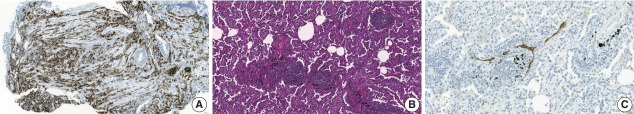

Treatment challenges persist in advanced lung cancer despite the development of therapies beyond the traditional platinum-based chemotherapy. The early 2000s marked a shift to tyrosine kinase inhibitors targeting epidermal growth factor receptor, ushering in personalized genetic-based treatment. A further significant advance was the development of immune checkpoint inhibitors (ICIs), especially for non-small cell lung cancer. These target programmed death-ligand 1 (PD-L1) and cytotoxic T lymphocyte antigen 4, which enhanced the immune response against tumor cells. However, not all patients respond, and immune-related toxicities arise. This review emphasizes identifying biomarkers for ICI response prediction. While PD-L1 is a widely used, validated biomarker, its predictive accuracy is imperfect. Investigating tumor-infiltrating lymphocytes, tertiary lymphoid structure, and emerging biomarkers such as high endothelial venule, Human leukocyte antigen class I, T-cell immunoreceptors with Ig and ITIM domains, and lymphocyte activation gene-3 counts is promising. Understanding and exploring additional predictive biomarkers for ICI response are crucial for enhancing patient stratification and overall care in lung cancer treatment.